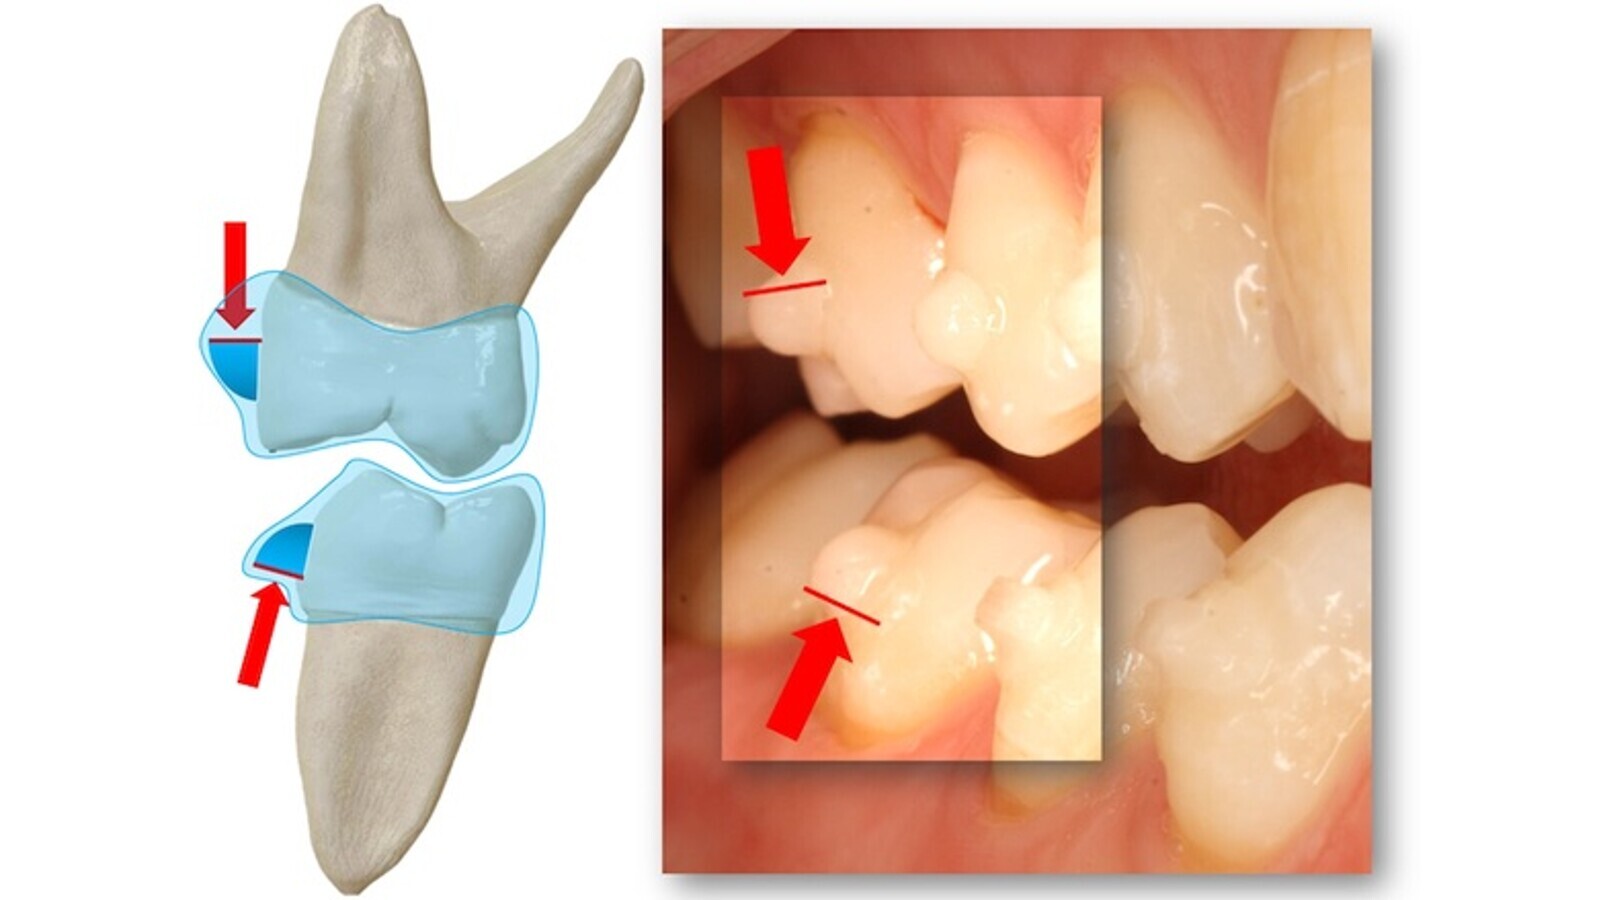

Un punto clave del diseño y planificación digital de alineadores es la colocación de los ataches y puntos de presión. Hay que entender que si bien la biomecánica ortodóncica obedece a una bases conceptuales y clínicas comunes, esta ha de adaptarse a los diferentes aparatos y sistemas. Si, por ejemplo, queremos realizar un movimiento de inclinación controlada vestíbulo-palatino de un incisivo central superior (figura 1) podemos recurrir a la técnica multibrackets clásica con un arco redondo, a una placa removible activa con un arco vestibular o a un alineador.

Figura 1. Movimiento de inclinación controlada vestíbulo-palatino de un incisivo central superior con técnica multibrackets clásica, con placa removible activa o con alineador.

En los tres casos queremos que el centro de rotación (C Rot) se sitúe en el ápice dentario y que la distancia entre el punto de aplicación de la fuerza y el centro de resistencia del diente (C Rs) nos genere un momento o giro de la corona en la dirección deseada.

En los tres casos, la fuerza la aplicamos en la superficie labial del diente, pero en los alineadores tenemos la enorme ventaja de que el polímero rodea a toda la corona dentaria, teniendo un mayor control sobre la misma (hay un cierto espacio virtual entre diente y plástico). Sí hay que tener en cuenta que el alineador ha de poderse quitar con facilidad y por tanto el diseño de los ataches no puede generar una retención que dificulte esta maniobra. La actuación de las fuerzas, y su descomposición biomecánica, sobre la interfase atache-alineador es un sistema determinado y puede analizarse, al menos experimentalmente, con modelos de simulación matemática como los elementos finitos. Si bien algunas compañías han patentado los diferentes ataches y les han dado sugestivos nombres propios de una película de agentes secretos, con el único y espurio objetivo de marketing, las cosas son mucho más sencillas de lo que parecen y obedecen a leyes físicas simples y fáciles de modelizar matemáticamente por la isotropía de los mismos ataches. Un atache triangular escaleno sobre el que incide la fuerza del alineador en el lado más largo, acaba descomponiendo esta fuerza perpendicular en dos vectores (uno de retrusión palatina y otro de extrusión) y, en la práctica, el polímero potencia o anula el efecto de alguno de ellos (figura 1).